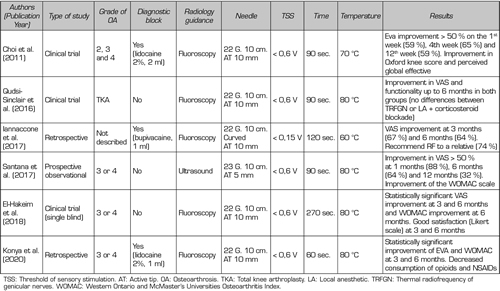

Effectiveness of thermal radiofrequency of genicular nerves

The first study that reported improved pain in patients after TRF of the genicular nerve (SMGN, SLGN, and IMGN) was performed by Choi et al. (9). They observed a reduction in pain higher than 50 % in the first, fourth and twelfth weeks (59, 65 and 59 %, respectively) (Table IV).

Table IV. Efficacy of thermal radiofrequency of genicular nerves

Other studies were then developed finding that pain reduction could be maintained up to one year. Iannaccone et al. (15) found not only an improvement in pain at three months in 67 % of patients, but a maintenance of this relief in 95 % of patients up to six months. Santana et al. (14) found a monthly improvement in pain in 88 % patients and at six months in 64 % of the patients studied. However, this benefit decreased progressively after six months, finding that 32 % of patients had an improvement in pain after a year, without reaching the level of pain they had prior to TRF.

Although the decrease in the pain scale is one of the most important parameters for assessing the efficacy of TRFGN, we should not forget to quantify other values that also inform us of the effectiveness of ablation of genicular nerves such as: improved functional capacity, good patient satisfaction, and decreased analgesic use. El-Hakeim et al. (25) compared TRFGN with conventional oral analgesic treatment, finding not only a statistically significant improvement in pain relief, but also an improvement in quality of life using the WOMAC scale and good patient satisfaction up to six months of follow-up. However, this study is limited by not having a pre-TRFGN prognostic block and not being a double-blind study. Konya et al. (26) found an improvement in quality of life in 79 % of patients, but also a decrease in VAS to 2 points at six months associated with a decrease in NSAID use in 40 %. achieving the abandonment of these by 50 %.

Another population that can benefit from TRFGN are patients who have pain after TKA. Protzman et al. (27) first described pain relief and improved quality of life after using ultrasound-guided and fluoroscopic-tested TRFGN in a patient with persistent knee pain after TKA. Qudsi-Sinclair et al. (24) confirmed these findings in a clinical trial conducted in 28 patients with knee pain refractory to medical treatment after TKA; the highest improvement was achieved at three months, subsequently with a progressive decrease in analgesic effect without losing it completely until one year of follow-up.